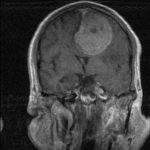

Cette masse peut entrainer notamment :

- Une irritation du cerveau qui se manifeste par une épilepsie

- Une compression voire destruction d’une partie du cerveau causant un affaiblissement ou une perte d’une fonction du cerveau

- Une augmentation de la pression à l’intérieur du crâne (espace inextensible à l’intérieur duquel vient s’ajouter le volume de la tumeur), ce qui va se manifester initialement par des maux de tête d’aggravation progressive qui vont s’associer à des nausées, des vomissements, des troubles visuels… Cet état peut aboutir à la perte de la vue dans les formes d’évolution lente et au décès dans les formes d’évolution rapide.